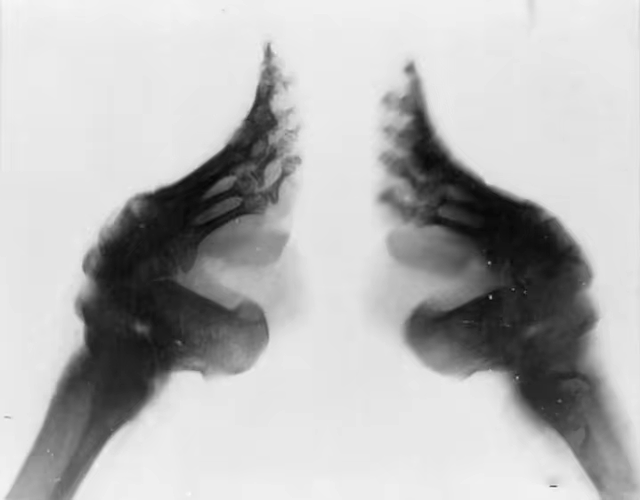

让我们先简单了解一下缠足的历史。缠足大致起源于宋代,底层劳动者尚且不需要缠足,于清朝时到达巅峰,缠足妇女们依旧需要拖着残破的身体下地干活。

缠足缠得好的人家“有出息”“有面子”,若是不缠足就是“浪脚”,就嫁不出去,所以妇女们不得不忍受着断骨蚀肉之痛以追求那“三寸金莲”。

因为脚部神经受损会导致腿部肌肉萎缩,再加上小脚走路时的锥心之痛,这样能有一番“若柳扶风”之姿。就像西方的束腰一样,病态的身体导致的苍白面孔与殷红嘴唇,死亡时达到标准的“美人”,这些是当时流行于世的普遍审美,甚至会有人追求意外的死亡以让自己登上美人之列。